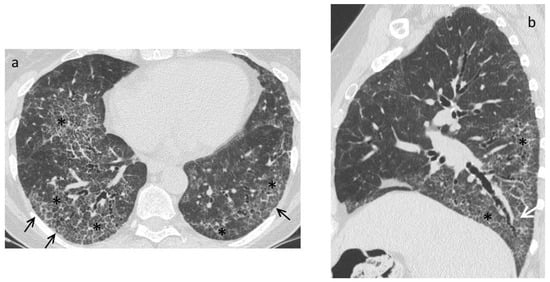

| Early stage | NSIP pattern:

|

| Late fibrotic stage | Fibrotic NSIP/UIP pattern: